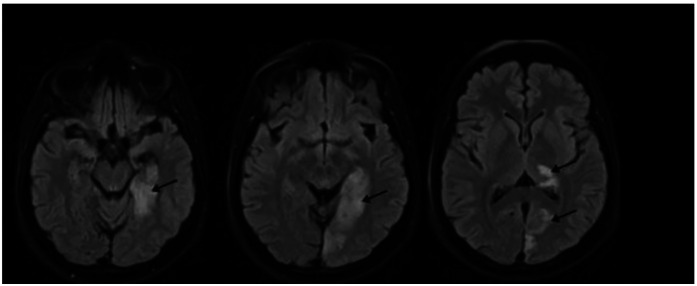

Case description: A 30-year-old transgender female patient had been using estrogenic HT purchased on the black market (cyproterone 2 mg + ethinyl estradiol 0.035 mg/day) since the age of 17, without medical supervision. She had a history of HIV infection under irregular treatment and previously treated syphilis. She developed sudden-onset right-sided hemiparesis and homonymous hemianopsia. The initial computed tomography scan revealed no abnormalities, but magnetic resonance imaging showed ischemia in the territory of the left posterior cerebral artery. Etiological investigation with echocardiography, carotid and vertebral Doppler ultrasound, electrocardiogram, Holter monitoring, and thrombophilia panel revealed no abnormalities. The final etiological diagnosis was classified according to the TOAST criteria as "other causes," attributed to the inappropriate use of estrogenic therapy. She was discharged with antiplatelet therapy, a statin, and fluoxetine, along with the discontinuation of hormone therapy and referral to transgender and vascular neurology outpatient clinics.